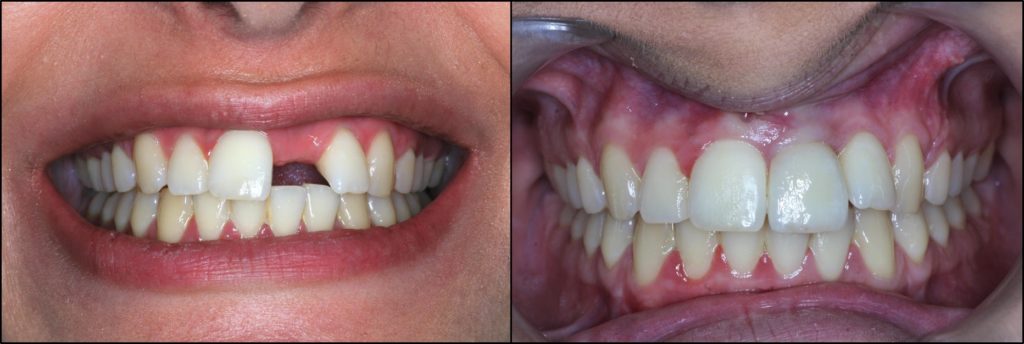

Περίπτωση αποκατάστασης μονήρους απώλειας του κεντρικού τομέα της άνω γνάθου σε νέα γυναίκα με υψηλή γραμμή χαμόγελου και υψηλές αισθητικές απαιτήσεις. Η συγκεκριμένη περίπτωση αντιμετωπίστηκε με μόσχευμα σκληρών και μαλακών ιστών, ενώ κατασκευάστηκε ολοκεραμική στεφάνη για την επίτευξη του ιδανικού αισθητικού αποτελέσματος (Προσθετολόγος: Α. Μητσούδης).